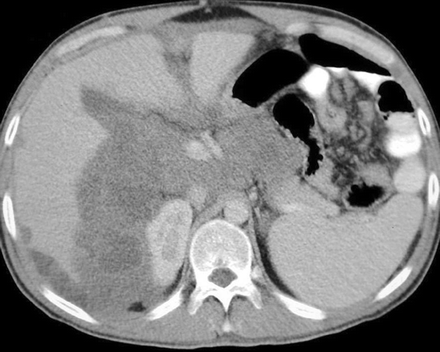

Peritoneal mesothelioma has two clinical types which can be differentiated with the help of CT findings, the "dry" type, and the "wet". It is classified as "dry" when there are multiple tiny masses or one dominant localized mass and generally little or no ascites. The "wet" type has widespread small nodules, no dominant mass, and a presence of ascites. If fluid is found, the process of eliminating it is through paracentesis; however, the analysis of this fluid has limited diagnostic significance. Normally, a definitive diagnosis may be obtained through tissue biopsy.